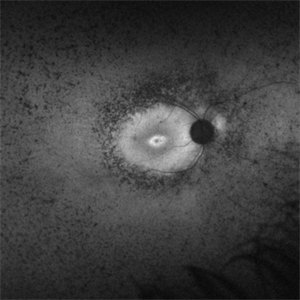

Retinitis Pigmentosa Bullseye Appearing Autofluorescence

Feb 4 2025 by Isaac Agranoff

Fundus Autofluorescence of a 14-year-old boy with suspected RP. ERG performed afterwards was almost flat. VA measured at 20/30 but with extensive constriction of confrontational visual fields. Currently awaiting genetic testing.

Photographer: Isaac Agranoff

Imaging device: Optos California

Condition/keywords: fundus autofluorescence (FAF), retinitis pigmentosa, RP